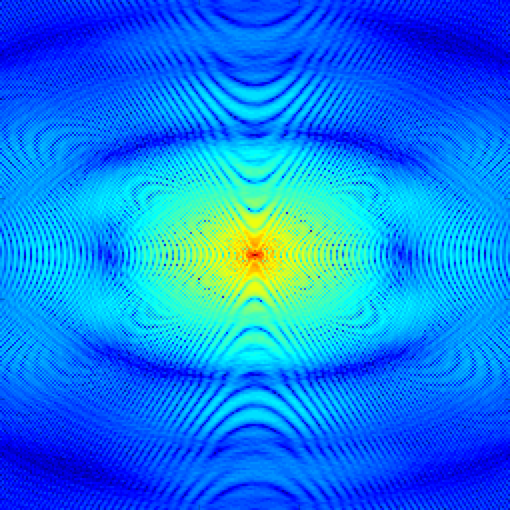

In Fig. 2 we demonstrate the ability of the proposed algorithm to recover a piecewise constant signal from few of its uniform low-resolution Fourier samples. We experiment on simulated data obtained from analytical MRI phantoms derived in [13]. We extrapolate from analytical Fourier samples of the Shepp-Logan phantom to a grid (20-fold undersampling), and recover the signal by performing a inverse DFT. Note that the ringing artifacts observed in the recovery are to be expected due to fact we are recovering exact Fourier coefficients of the signal, and could be removed with mild post-processing.